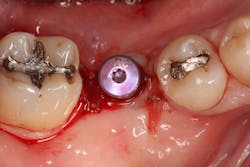

The patient returned for a two-week suture removal and was given an ultrasoft postsurgical brush. The patient continued chlorhexidine gluconate 0.12% rinses for one week and was instructed to brush the adjacent teeth and gums with the postsurgical brush for one week. The patient was then told to resume normal hygiene in the area and discontinue chlorhexidine gluconate 0.12% a week after suture removal (i.e., three weeks from surgery).

The patient was seen four months later for Stage II uncovering of her implant using a tissue punch and was sent to her restorative dentist for final impressions two weeks after that. Three months after the initial surgery, the patient returned with her final restoration in place for a soft-tissue exam and radiograph. Six months after surgery, she returned for a postdelivery radiograph, shown here. (I see every implant patient three months after seating the final restoration to check for residual cement, ensure that the restorative apparatus is fully seated, and check the soft- and hard-tissue response to the new restoration. This is an extremely important—and often overlooked visit—where problems are often noted that can cause significant damage to the bone and gingiva if early intervention is not initiated.) The bone levels were well-maintained around the implant platform, and the soft-tissue health was excellent. The patient reported a high degree of satisfaction with her new implant restoration.